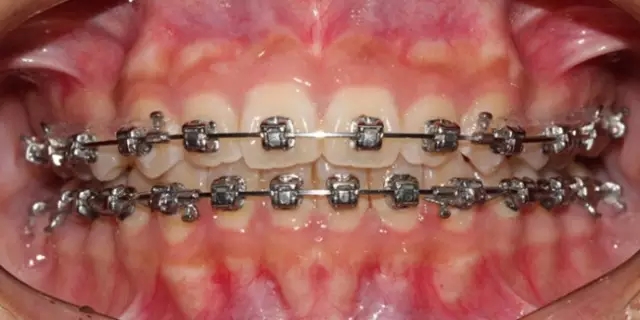

Damon 病例分享:安氏 II 類二分類露齦笑的矯治(董一磊)